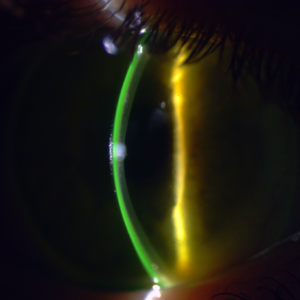

- Jak ocenić dopasowanie soczewek ortokorekcyjnych

- Jak analizować mapy rogówki pod kątem soczewek ortokorekcyjnych?